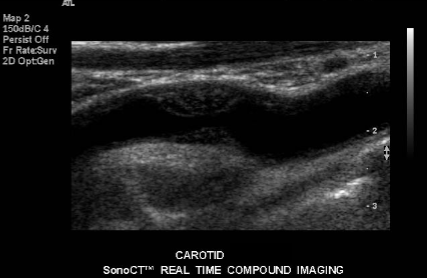

Evaluate closely for the sonographic finding seen in the carotid here.

Low-level echoes of soft plaque